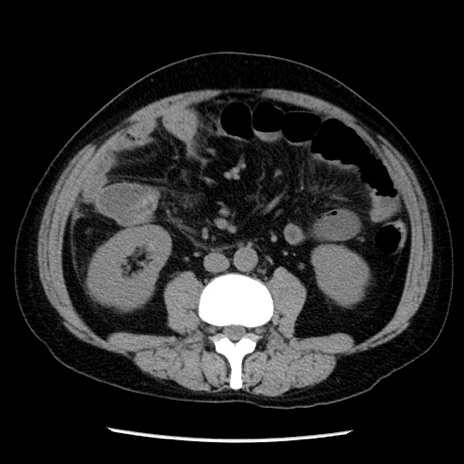

症例29(横断像)

【症例】40歳代男性

【現病歴】2日前から胃痛あり。徐々に周期的な激痛に変化した。本日になっても激痛があるため受診。

【身体所見】意識清明、BT 38-39℃台あり、腹部:膨満、やや硬、右下腹部に圧痛あり。

【データ】WBC 8500、CRP 23.26